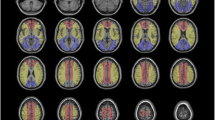

ASL score and relevant imaging features

The preoperative ASL images were graded on 2 slices corresponding with the ASPECTS locations using a 4-point scoring system as follows: 0, no or minimal ASL signal; 1, low/moderate ASL signal with ATA; 2, high ASL signal with ATA; and 3, normal perfusion without ATA [13]. Several slices immediately above and below the precise ASPECTS slice were checked to improve the robustness of this scoring system [13]. This grading was performed in 10 cortical regions in the ipsilateral hemisphere of surgery, and the overall ASL score ranged from 0 to 30 (two cases in Figs. 5 and 6 are for reference). Two radiologists with 19 and 7 years of experience in neuroradiology independently evaluated the ASL score, blinded for the clinical and other imaging information. Disagreements were resolved by consensus. To assess intra-observer variability, one observer reviewed the same ASL images of 69 patients included from May 2015 to January 2021 (3 months apart).

A representative case of cerebral hyperperfusion symptom (CHS). a A patient with right carotid stenosis. b, c Arterial spin labeling (ASL) score based on arterial transit artifacts on two slices corresponding to the ASPECT score locations. The total ASL score was 16 points. d Cerebral blood flow ratio map shows hyperperfusion in the ipsilateral middle cerebral artery territory. Preoperative computed tomography angiography (a), MR angiography (e, f), and fluid-attenuated inversion recovery (g, h) show carotid near occlusion (arrow), absence of the anterior communicating artery (arrowhead), opening of the ipsilateral posterior communicating artery (curved arrow), and leptomeningeal collaterals (oval). i Postoperative MR angiography shows a decrease in the signal of the ipsilateral posterior communicating artery (asterisk) after surgery. This patient further developed CHS

A case of late-onset cerebral hyperperfusion symptom (CHS). a Computed tomography angiography shows right carotid artery severe stenosis (arrow). The preoperative arterial spin labeling (ASL) score was 6 points (b, c), and cerebral hyperperfusion was determined by cerebral blood flow (CBF) ratio maps (d, e). This patient had no symptoms or signs related to CHS during the first hospitalization. On the 24th day after surgery, the patient was re-admitted to hospital due to CHS with a systolic blood pressure of 190 mmHg. Fluid attenuation inversion recovery (f) shows regional swelling of the ipsilateral parietal and occipital lobe (curved arrow), and the CBF of the right occipital lobe was higher than that of the left (g). After treatment, the regional swelling disappeared (h) and the CBF of the right occipital lobe decreased to normal (i). j Changes in systolic blood pressure during two hospitalizations. BP0, baseline blood pressure; BP1, blood pressure within 24 h after surgery; BP2, maximum blood pressure after surgery during the first hospitalization; BP3, blood pressure at the first discharge; BP4, blood pressure on re-admission (down arrow); BP5, blood pressure within 24 h of re-admission; BP6, maximum blood pressure after 24 h during the second hospitalization; BP7, blood pressure at the second discharge